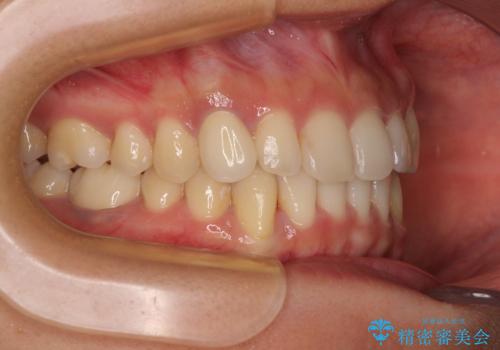

- 下顎の八重歯を気にして来院された患者様です。

マウスピース矯正でもワイヤー矯正でも対応可能であり、マウスピースによる治療を希望されたため、インビザラインを用いることとしました。

下顎前歯にデコボコが集中していたため、顎間ゴムによる後方移動とIPR(歯と歯の間を削ること)により歯列を整えることとしました。

しっかりとマウスピースを装着してくださったおかげで、スムーズに治療を終えることができました。

矯正治療途中で右下奥歯の虫歯治療を近医で行ったようで、既に神経が失活していたと合わせて矯正治療後に補綴治療を行う予定です。